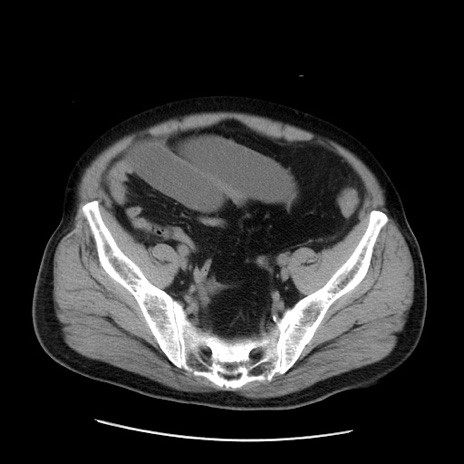

症例20(横断像)

【症例】 60歳代男性

【主訴】 腹部膨満、嘔吐

【現病歴】5日前頃より倦怠感を認め食事量減少し4日前の朝嘔吐、食事摂取困難となった。 3日前近医受診し点滴施行され整腸剤などを処方された。 当日他院を受診し、腹部膨満著明、炎症反応の上昇(CRP10.8、WBC11200)あり、紹介受診となる。

【身体所見】 意識JCS1 受け答えがはっきりしないBP 111/57mHg、 P 67bpm、、BT35.2°C、SpO2 97%(RA)、 腹部:膨隆、打診で鼓音あり、全体的に圧痛有り、腸蠕動音(-)、反跳痛ははっきりせず。

【データ】WBC 11400、CRP 14.20